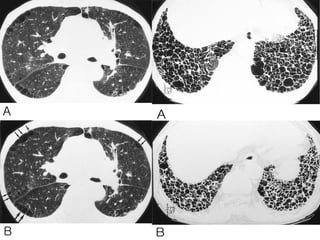

Upper lobe Bulla

Lower lobe Bulla

A: Xray shows bilateral bulla.

B: CT shows bilateral bulla.

C: CT after bullectomy.